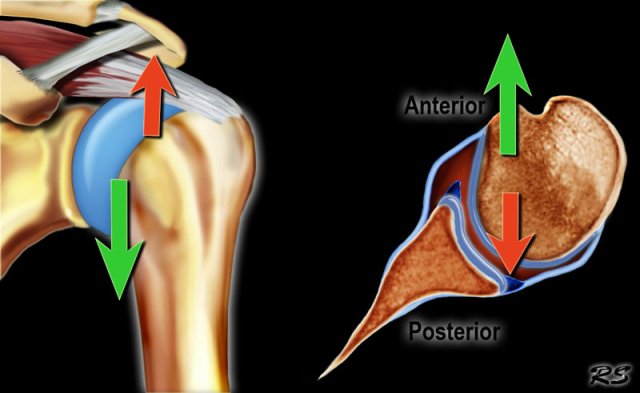

Anterior dislocation

The shoulder almost always dislocates to anterior and inferior, because motion to superior is limited by the acromion, coracoid process and rotator cuff (figure).

Motion in a posterior direction is limited by the posterior rim of the glenoid which is in an anteverted position.

The dislocation of the humeral head to antero-inferior causes damage to the antero-inferior rim of the glenoid in the 3 - 6 o'clock position (marked in red).

Especially in younger patients this results in a Bankart fracture or a Bankart lesion which is a tear of the anteroinferior labrum.